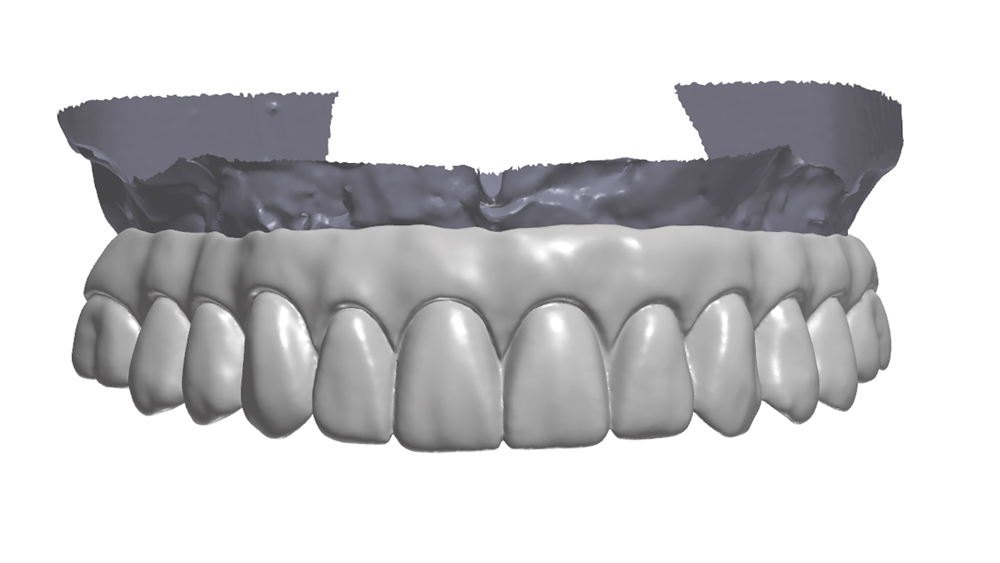

Once osseointegration is complete, the BruxZir® Full-Arch Implant Prosthesis is the ideal choice for the restoration, as its monolithic construction prevents chips, stains, breakage, and dislodged or worn-down prosthetic teeth.3,4 This treatment option has helped elevate the quality of care I’m able to provide for my edentulous patients, who no longer return to my office with a broken acrylic appliance in hand.